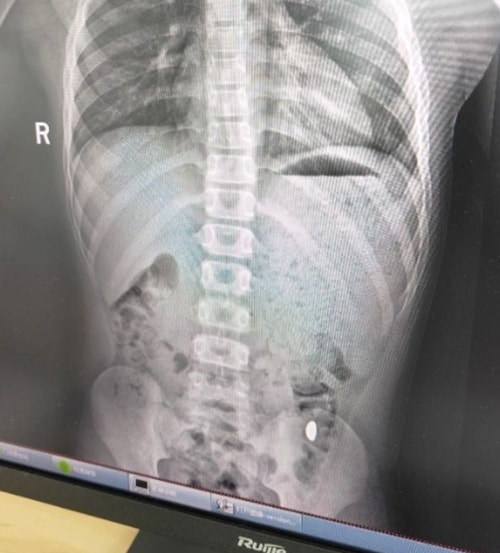

Tuy nhiên, sau 5 ngày liên tục kiểm tra phân của con hai lần mỗi ngày, cô vẫn không thể tìm thấy vàng. Hôm 26/10, Ji đưa con trai đến Bệnh viện Nhân dân số 5 Côn Sơn để kiểm tra, phát hiện "vật thể lạ trong dạ dày". Cuối ngày hôm đó, hạt đậu vàng được lấy ra thành công. Bác sĩ cảnh báo nếu ở lại quá lâu, dị vật có thể gây tắc ruột và yêu cầu gia đình tiếp tục theo dõi.